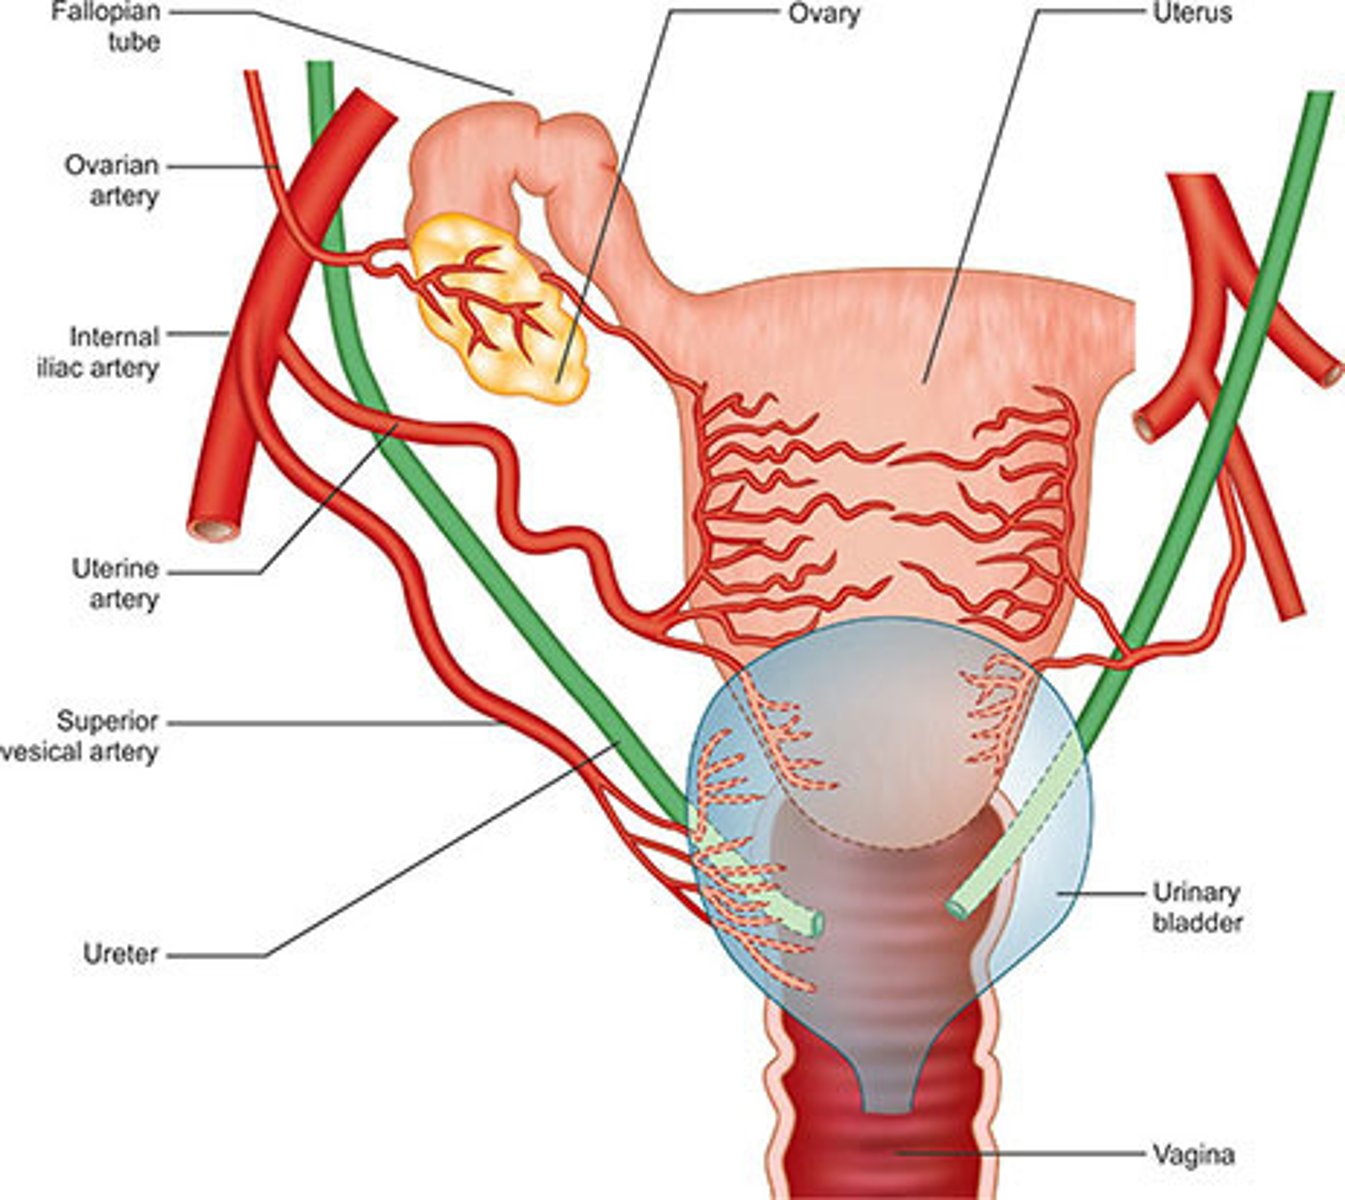

Ovaries are located in the ___ within the ___

adnexa; true pelvis

Ovaries are ___ to the internal iliac arteries and ___ to ureters

medial; anterior

The broad ligaments extend between the ___ and ___

uterine body; ovary

What is positioned between the 2 layers of the broad ligaments?

fallopian tubes

round ligament

ovarian ligament vascular structures

The round ligaments are located ___ to the fallopian tubes and insert into the ___ to help maintain the ___ of the uterus

anteroinferior; labia majora; position

The ovarian ligaments are located ___ at the ___ of the uterus

bilaterally; cornua

The suspensory ligaments extend from the ___ to the ___

infundibulum; pelvic sidewall